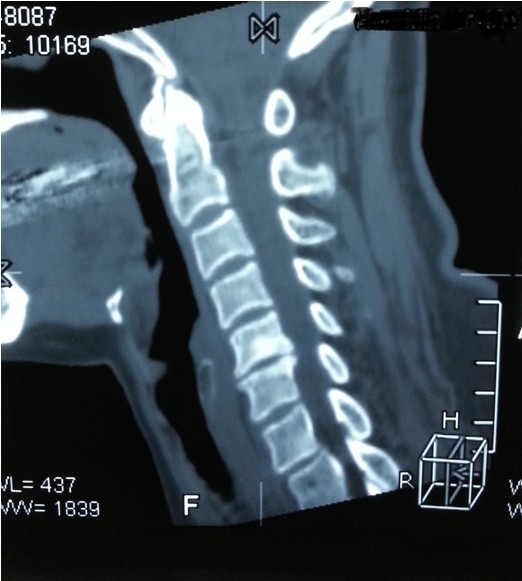

我院副院長兼脊柱科主任劉志安詢問病史后,詳細查體并攝片,發(fā)現(xiàn)患者是頸椎間盤突出,骨質增生,壓迫頸椎神經(jīng),引起頸肩部酸脹難忍,雙手麻木乏力,若不盡快處理,癥狀將進一步加重,建議患者盡早手術治療,否則將喪失最后的手術時機,有致癱瘓的可能。

一開始,處于對手術以及住院費用的恐懼,患者要求保守治療,可是如此嚴重的椎間盤突出,保守治療根本無法解除對頸椎的神經(jīng)的壓迫。劉副院長詳細向患者講述其病情起因,發(fā)展,變化,轉歸,并表示,患者頸椎手術總費用預計在5萬以內,報銷后自費約4萬左右,考慮患者家庭困難,可聯(lián)系紅十字基金會予以適當?shù)难a貼,考慮再三,最終患者選擇到我院手術治療。手術結束后,患者慢慢開始恢復,頸肩部酸脹不適癥狀消失,雙手麻木乏力癥狀較術前大為緩解,兩周后出院,患者及家屬對手術治療效果,醫(yī)生護士服務態(tài)度,以及花了3萬元就解決困擾多年的疾病均表示非常滿意。